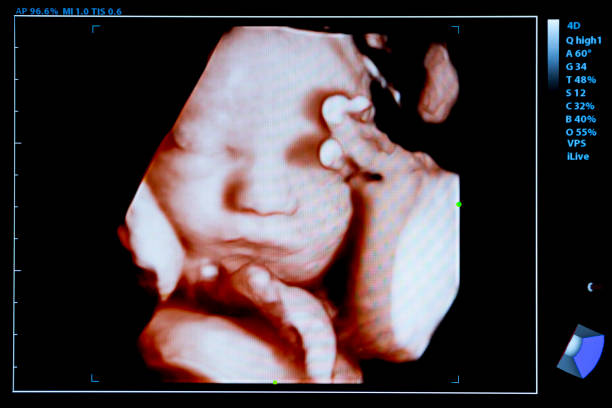

習(xí)慣性流產(chǎn)是指女性連續(xù)發(fā)生兩次或以上自然流產(chǎn)的情況,這不僅對身體造成傷害,也給心理帶來了極大的壓力和困擾。對于有習(xí)慣性流產(chǎn)史的夫妻來說,選擇合適的生育方式尤為重...

習(xí)慣性流產(chǎn),即連續(xù)兩次或兩次以上在妊娠20周前自然終止妊娠,給許多家庭帶來了沉重的心理和經(jīng)濟負擔(dān)。試管嬰兒技術(shù)作為一種輔助生殖技術(shù),為這些家庭帶來了新的希望。然...

習(xí)慣性流產(chǎn),即連續(xù)兩次或兩次以上在妊娠20周前發(fā)生自然流產(chǎn)的情況,對于許多家庭來說,是一個沉重的打擊。面對這一困境,許多夫婦可能會考慮采用輔助生殖技術(shù),如試管嬰...

在我國,習(xí)慣性流產(chǎn)是指連續(xù)發(fā)生3次或3次以上的自然流產(chǎn)。對于習(xí)慣性流產(chǎn)的患者來說,試管嬰兒技術(shù)是一種常見的治療手段。那么,習(xí)慣性流產(chǎn)做試管需要多少錢呢?以下將從...

習(xí)慣性流產(chǎn)是指連續(xù)發(fā)生兩次或兩次以上的自然流產(chǎn),這通常會給患者及其家庭帶來極大的心理壓力和生活困擾。對于有習(xí)慣性流產(chǎn)史的患者來說,三代試管嬰兒技術(shù)提供了一種可能...

習(xí)慣性流產(chǎn)是指連續(xù)發(fā)生三次或以上的自然流產(chǎn),這通常會給患者及其家庭帶來極大的心理和經(jīng)濟壓力。試管嬰兒技術(shù)作為一種輔助生殖技術(shù),為習(xí)慣性流產(chǎn)的患者帶來了新的希望。...

習(xí)慣性流產(chǎn),即連續(xù)兩次或兩次以上自然流產(chǎn),對許多家庭來說是一個沉重的打擊。隨著輔助生殖技術(shù)的發(fā)展,三代試管嬰兒技術(shù)為這些家庭帶來了新的希望。那么,習(xí)慣性流產(chǎn)的患...

習(xí)慣性流產(chǎn),即連續(xù)發(fā)生三次或以上自然流產(chǎn),對于患者和家屬來說,無疑是一種巨大的心理和生理壓力。為了提高生育成功率,很多家庭會選擇進行試管嬰兒技術(shù)。其中,第三代試...